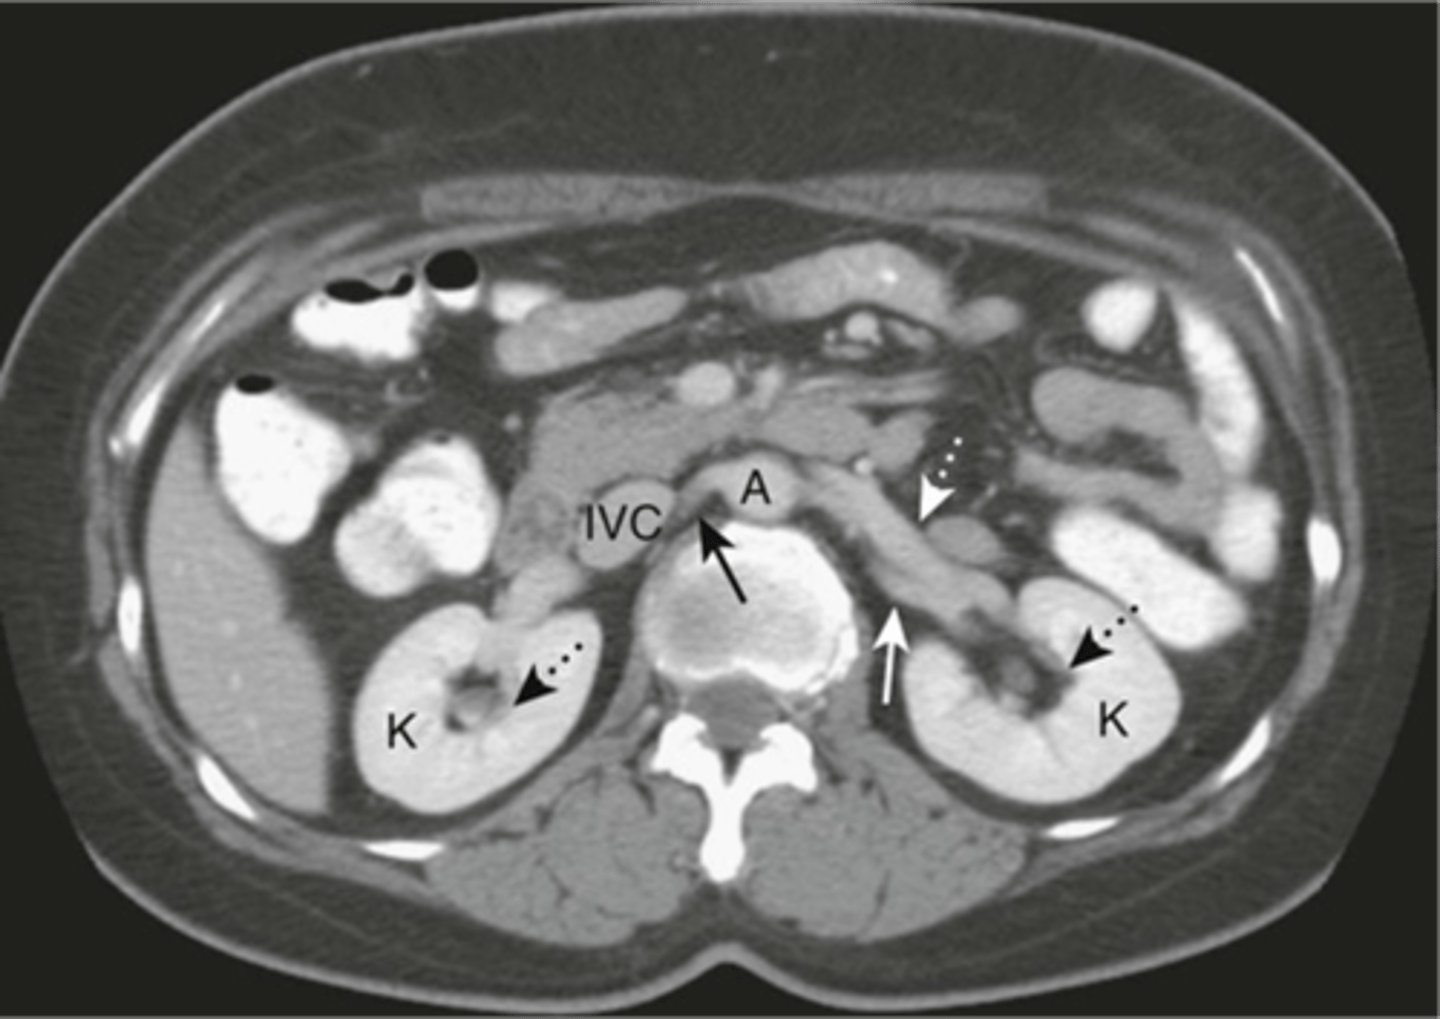

Abdominal aortic aneurysm on CT

Stent due to AAA